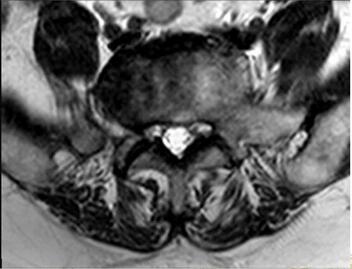

3.輔助檢查:CT(外院)顯示L4-L5椎間盤突出左旁中央型。

4.輔助檢查:MRI顯示腰椎退行性變:L4-5椎間盤脫出(左側(cè)隱窩型),伴左側(cè)側(cè)隱窩狹窄,相應(yīng)神經(jīng)根受壓,馬尾神經(jīng)受壓;局部腰椎管狹窄。